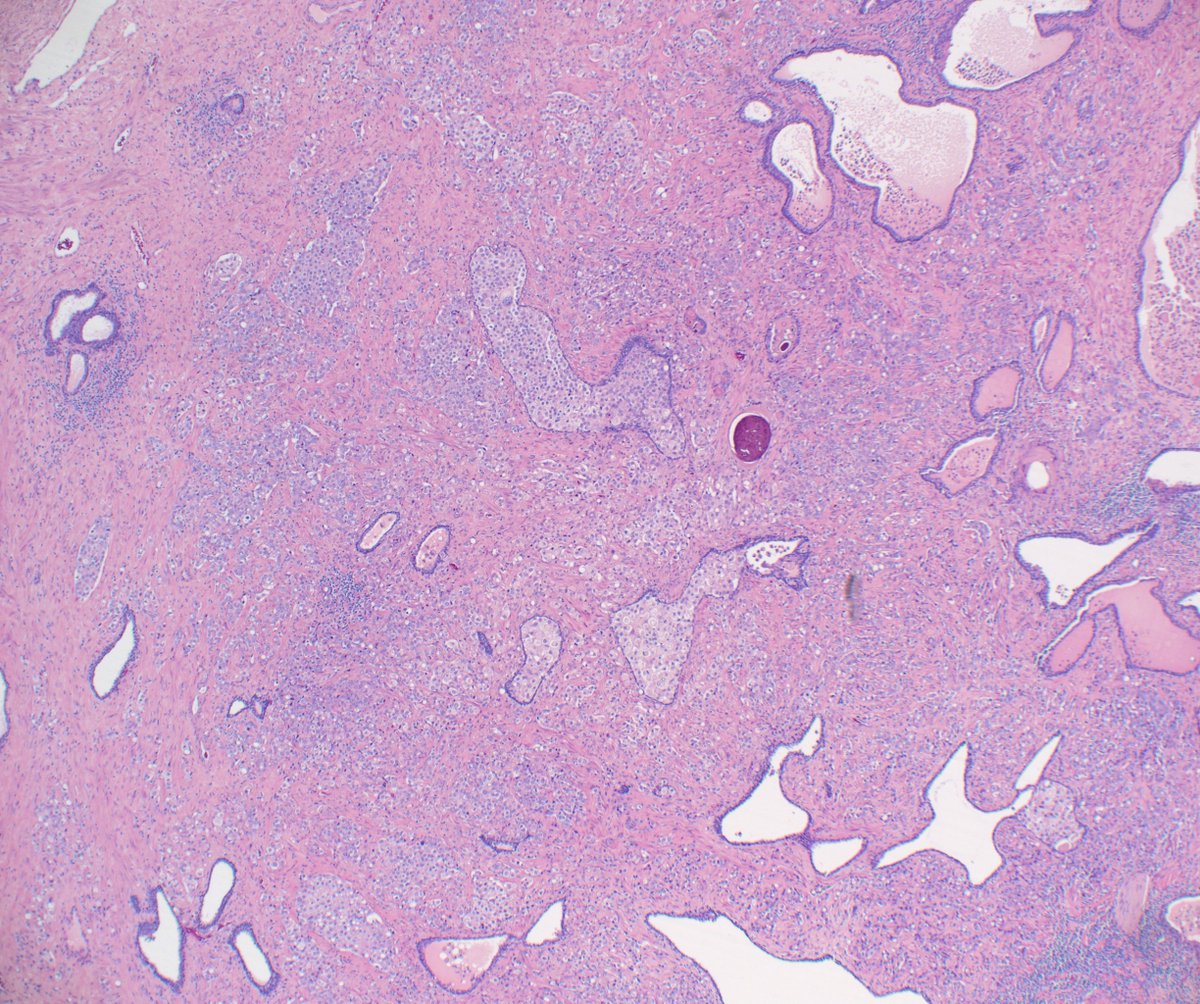

Glutamine Synthetase in liver, L to R: Normal Zone 3. Hepatocellular adenoma, some subtypes. Beta cat. HA-B, +GS. Tried to keep simple but found HA-I overlaps w/ FNH. Link to ref 👇 Focal nodular hyperplasia. Map-like GS, central scar, clin OCP. Photos HA-B, FNH PathologyOutlines.com